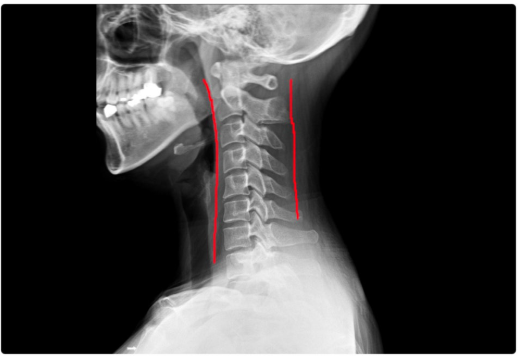

왜 일자목이 되면 온몸이 아플까요?

일자목이 되면 머리 무게를 지탱하는 근육과 인대에 부담이 크게 증가합니다.

정상적인 C자 곡선이 있을 때보다 2~3배 더 힘이 들어가 주변 근육 문제도 쉽게 생기죠.